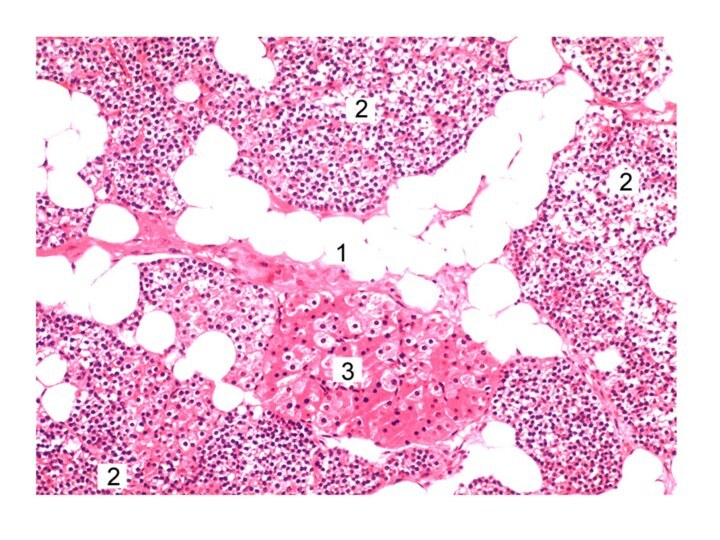

Препарат 2. Околощитовидная железа (окраска гематоксилином – эозином). Под малым увеличением

Под малым увеличением увидеть капсулу, эпителиальные тяжи или скопления

паратироцитов, а также липоциты, располагающиеся между эпителиальными клетками или в виде скоплений в прослойках соединительной ткани. Под большим увеличением рассмотреть главные и оксифильные паратироциты.